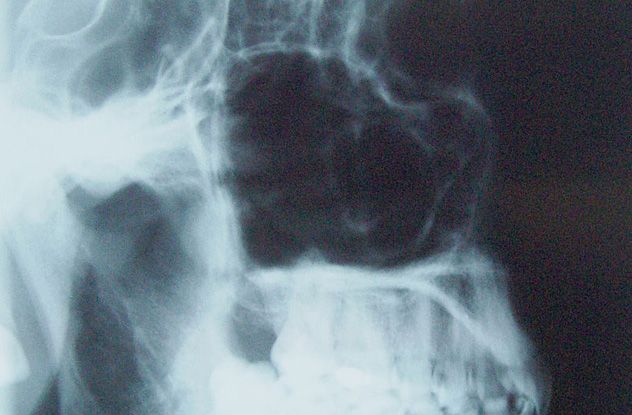

During their first visit, 90 percent of Weinberger’s patients were told they needed sinus surgery. Even those with minor sniffles left with holes drilled into their maxillary sinuses. Most of these procedures were unnecessary, and his outdated techniques often led to severe infections.

Weinberger’s actions went beyond negligence—he displayed psychopathic tendencies. He terrified patients with fabricated images of grotesque, bloody polyps in their sinuses. With no other surgeons in his practice and his own CAT scan machine, Weinberger maintained complete control, ensuring patients never sought second opinions.